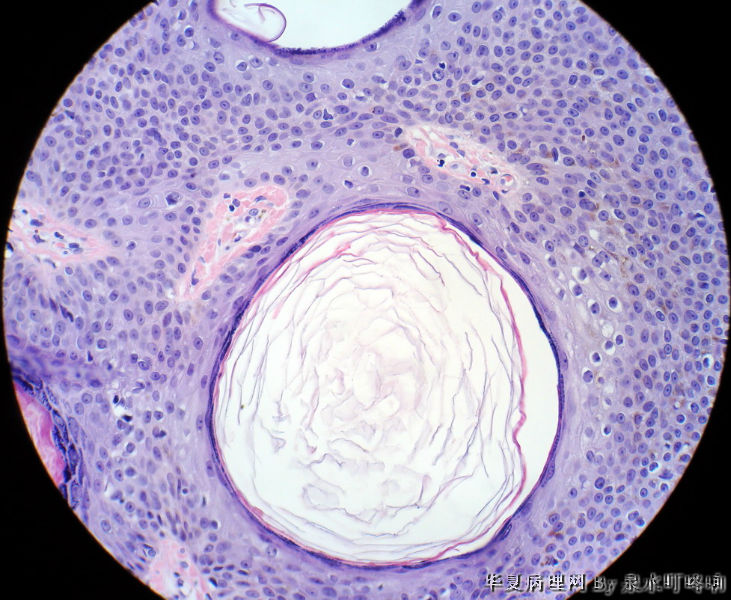

左耳后肿物

男,80岁,左耳后肿物十余年。左耳后肿物图1

棘层肥厚型脂溢性角化症

脂溢性角化病

同意脂溢性角化病,该例主要需要和汗孔瘤鉴别。

毛发上皮瘤

典型的棘层肥厚型脂溢性角化症!